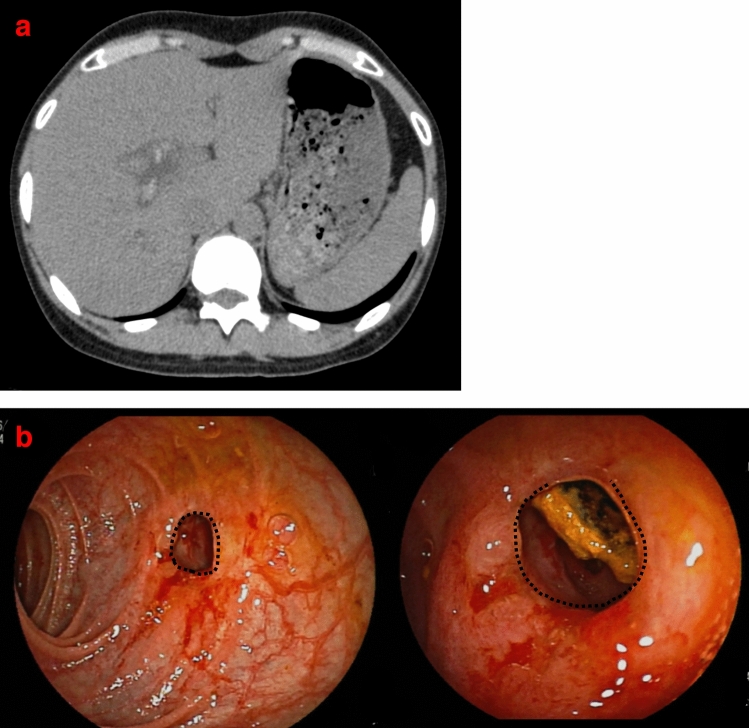

Diagnosis of strictures

Strictures were diagnosed as “bile duct strictures” if the presence of bile duct mucosa between the stenotic and anastomotic regions confirmed on endoscopy, and as “anastomotic strictures” if the mucosa was not present (Fig. 3).